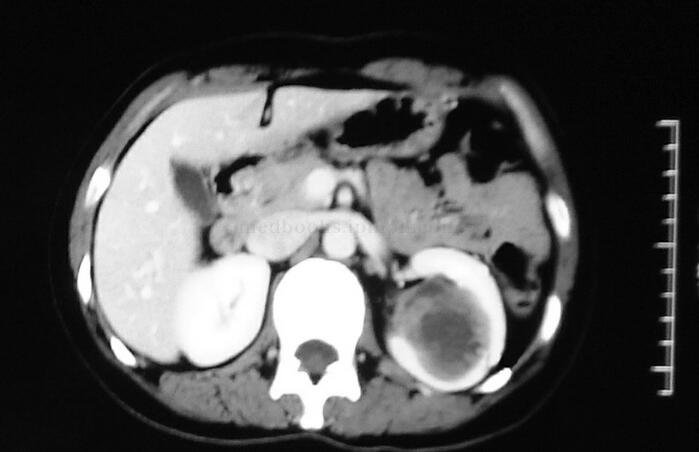

腹部计算机体层摄影(computed tomography,CT)(图10-1,图10-2):非增强扫描显示左肾体积略增大,左肾后下段可见一类圆形肿块影,包膜完整,密度不均匀,病变内散在类圆形及新月形低密度影,大小约4.3cm×4cm×4cm,周边可见花边样较高密度影;增强扫描显示低密度区未见明显强化,较高密度区可见轻度至中度强化,强化程度明显低于肾实质,周围肾实质明显受压变薄,左侧肾窦受压,肾窦内局部肾血管及肾盂、肾盏受压移位。经CT提示左肾占位性病变,合并局部出血。

图10-1 非增强扫描显示左肾密度不均的肿物